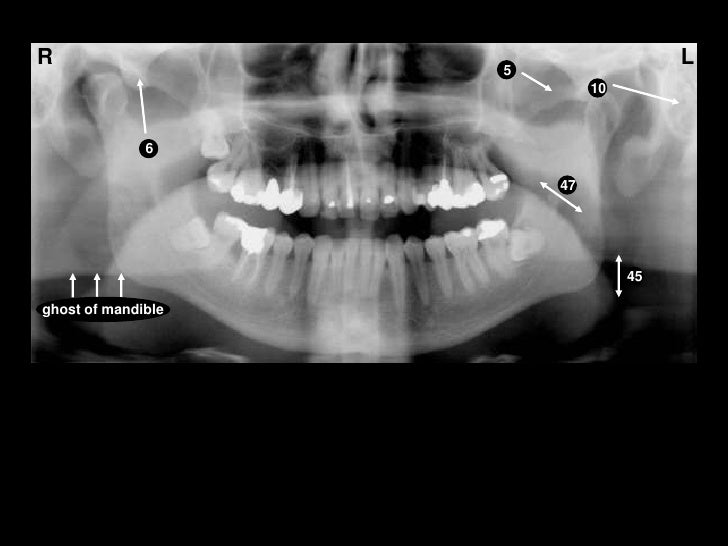

Self Study-pan-anatomy

mandible